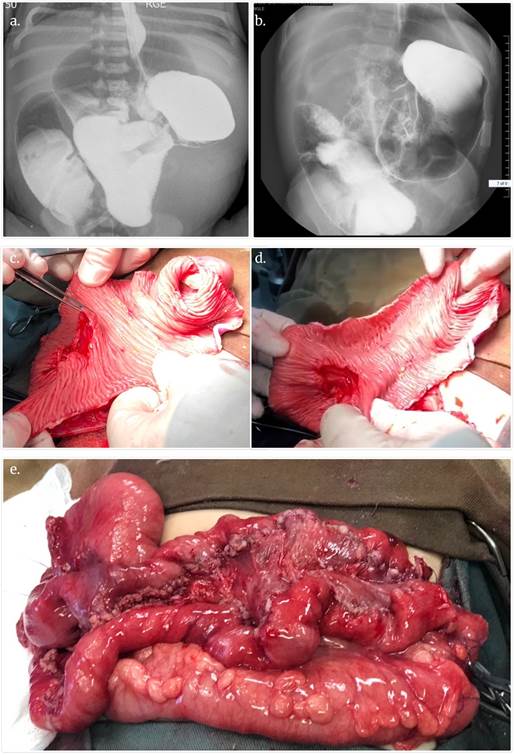

Se constata en la cirugía una longitud de 55 cm de yeyuno, de los que se seleccionan 35 cm dilatados con un diámetro de 5 cm (Fig.3). Se realiza elongación con misma técnica que caso clínico 1, logrando longitud intestinal final de 90 cm.

Fig.3 a y b) Estudio contrastado de intestino delgado que muestra marcada dilatación yeyunal prepoperatoria. c y d) Foto intraoperatoria del asa elegida para elongación, ya abierta por su borde antimesentérico, visualizándose la mucosa intestinal, y realizando apertura del borde mesentérico. e) Resultado final. Fuente autores